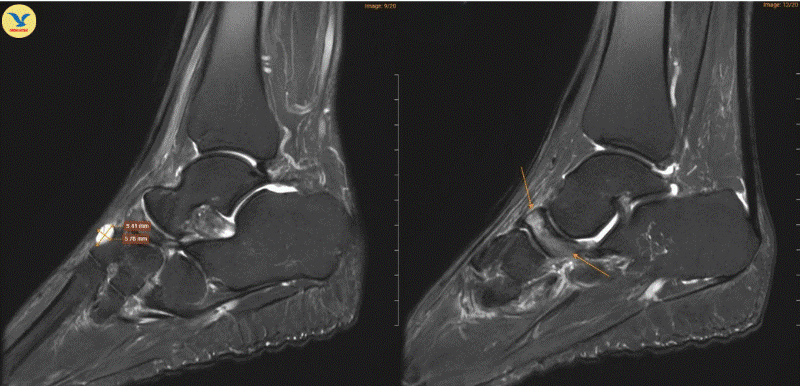

Đau khớp cổ chân khởi phát không rõ nguyên nhân, đi khám phát hiện Hội chứng Müller-Weiss hiếm gặp

(SKV) - Vừa qua, Hệ thống Y tế MEDLATEC phát hiện Hội chứng Mueller-Weiss hiếm gặp ở nữ giáo viên 52 tuổi. Đây là bệnh lý hoại tử xương ghe tự phát với tỷ lệ lưu hành trên thế giới dưới 1/1.000.000 dân, dễ bị bỏ sót hoặc nhầm lẫn với các bệnh lý xương khớp thông thường.